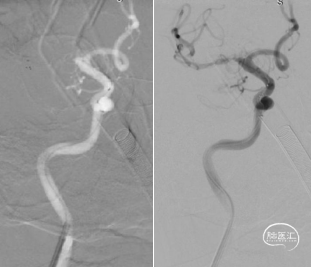

右侧大脑中动脉闭塞。

左侧颈内动脉显影正常,未见向右代偿。

右侧椎动脉优势,未见向前代偿。

考虑到血栓抽吸导管系统(ACE 68)头端抗抽瘪和优异通过性的特点,使用ACE 68快速高到位,微导丝携带微导管Rebar18 超选至R-M2段,造影证实在真腔。

造影考虑ICAS病变,通过微导管Rebar18输送5*30mm Reco取栓支架,施行SWIM技术。

SWIM技术取栓过程:ACE 68同轴到位M1起始段,回撤Reco取栓支架同时持续ACE 68向前跟进,减少血栓逃逸的同时将血栓拉进ACE 68并撤出体外。

一次取栓实现血管再通,复查造影提示R-M1局限性狭窄,观察20分钟复查造影R-M1局限性狭窄无明显回缩,前向血流III级,因前向血流速度正常,故原位狭窄暂不同期处理,待病情稳定后择期处理。